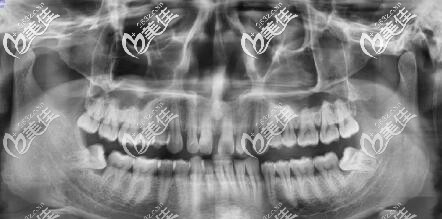

南昌男青年牙齒矯正之路,決定總是在一念間,我的牙齒是上門牙兩顆之間有個較大的縫隙,而且整體往左偏頜,南昌維樂口腔做的隱適美矯正,拔四顆智齒。

在做矯正的檢查時,居然發(fā)現(xiàn)我長了四顆智齒,還有兩顆斜著長的,拔了智齒才做矯正。

我一共才23套牙套,初戴牙套的感覺,說話有一點點大舌頭,后面就好了,還有前兩天牙齒有酸軟、很緊,每換下一幅牙套都有這個感覺,適應2天就好了。

等到戴第7副牙套的時候,牙齒就有變化了,原本縫隙較大的門牙,慢慢牙縫收起來了,也有一個很突的牙齒已經(jīng)慢慢收進去了。

現(xiàn)在戴到第20副牙套,看著牙齒每天一點點的移動發(fā)生變化就特別的高興。